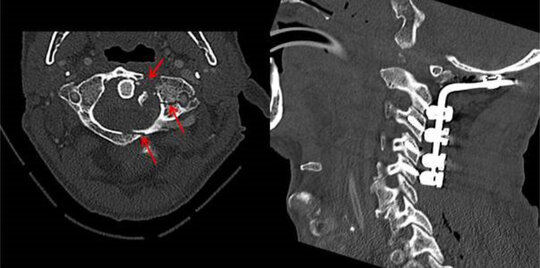

Stabilisierungen bei degenerativen Erkrankungen

Entsteht bei einer fortschreitenden Abnutzung der Bandscheibe oder anderen Verschleißerscheinungen eine zunehmende Lockerung zwischen zwei Wirbeln (degenerative Instabilität), kann sich diese Veränderung der Statik und Mechanik in einer schweren Rückenschmerzsymptomatik bemerkbar machen. Bei Diagnose einer degenerativen Instabilität ist häufig eine operative Stabilisierung erforderlich. Bei einer stabilisierenden Operation werden dann je nach Lokalisation und Ausprägung des Befundes verschiedene Materialien wie Schrauben, Platten oder Wirbelkörperprothesen eingebracht.

OPS bei Traumata, Entzündungen oder Tumoren der Wirbelsäule

Kommt es im Bereich der Wirbelsäule zu einem Trauma mit Fraktur (Knochenbruch), einer Entzündung der Wirbelkörper und Bandscheiben (Spondylodiszitis) oder einem Tumor mit Beteiligung der Knochenstrukturen, können aufwändige Operationen erforderlich werden. Ein Ziel dabei ist, dem Rückenmark oder den Nervenwurzeln den auf sie ausgeübten Druck zu nehmen. Dadurch sollen schwere neurologische Ausfälle bis hin zum Querschnitt oder zumindest eine Verschlechterung bereits bestehender Symptome vermieden werden. Zum anderen muss beim Vorliegen einer mechanischen Instabilität die Stabilität wieder hergestellt werden. Auch in diesen Fällen werden hierfür je nach Lokalisation und Befund Materialien wie Schrauben, Platten oder Wirbelkörperprothesen eingesetzt.